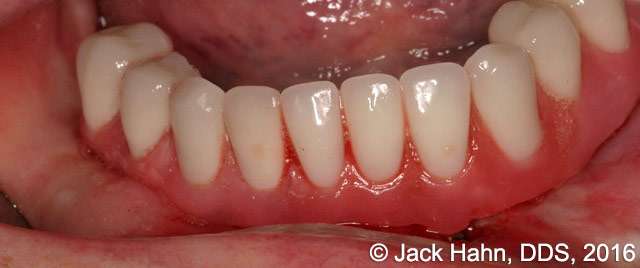

CASE #5 Laser Implant Exposure After Healing Abutments Come Off

This patient’s healing abutments came off in between appointments. In order to place the prosthesis, Dr. Hahn had to re-expose the implants. The photos were taken immediately before the exposure, immediately after the exposure, and after the placement of the prosthesis.

Implant exposures with LightScalpel dental lasers are quick and easy, saving Dr. Hahn valuable chair time. Some other benefits of performing Dental implant exposures with a LightScalpel laser include: it’s excellent coagulation ability; improved healing; minimized damage to surrounding tissues; diminished inflammation, swelling and pain; reduced risk of infection; and good patient acceptance.